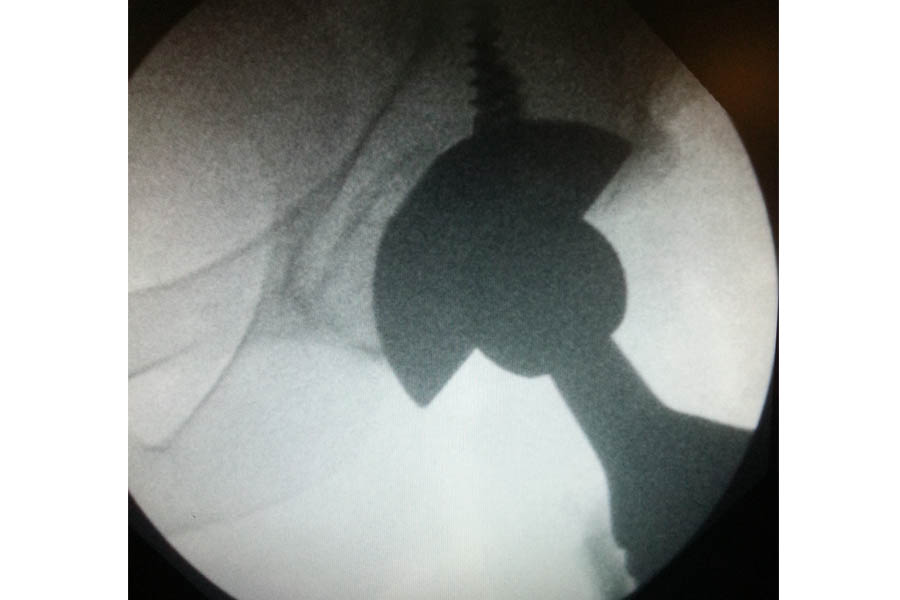

Total Elbow Replacement

Case 1